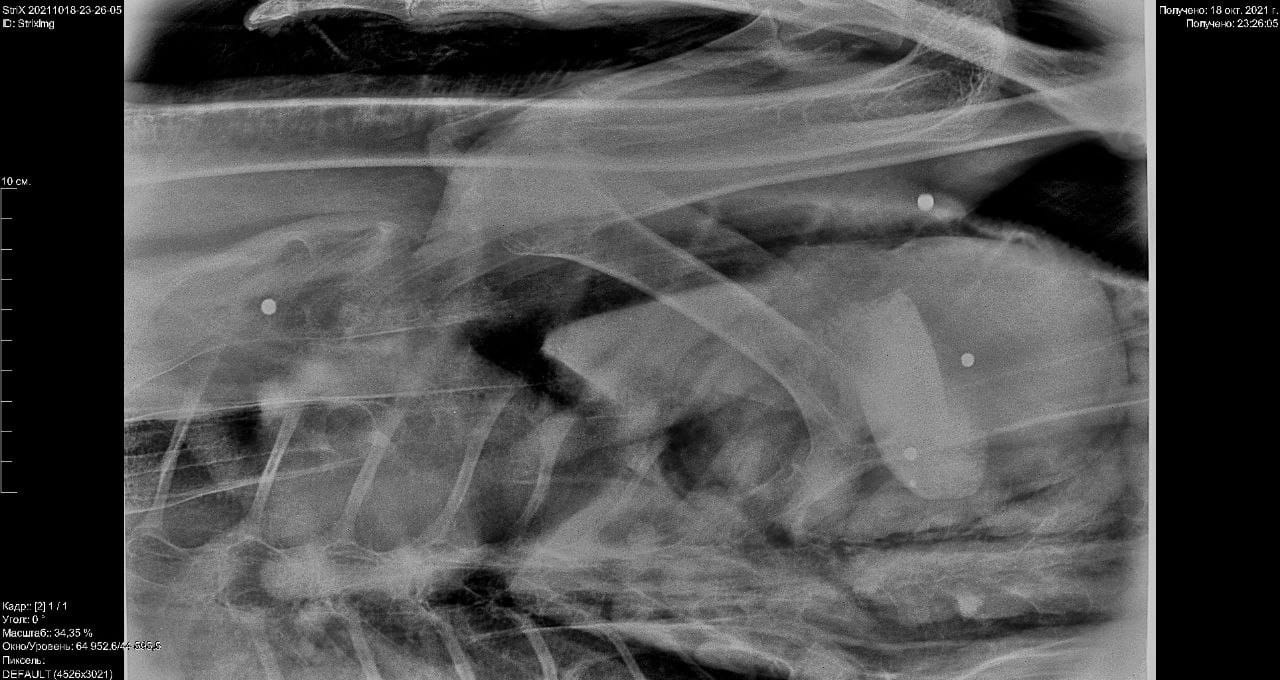

Огромная умная птица спокойно перенесла переезд в Центр реабилитации, где ее ждал рентген. Его итог печален: кликун получил заряд дроби 00.

У лебедина крыло пробито насквозь, и дробины застряли в туловище. Кости целы, но пара дробин вызывает сильные опасения тем, что они вероятно повредили кишечник. Это приговор...